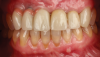

Five individual screw-retained milled ceramic crowns completed the all-digital treatment used to restore the patient without complication. As indicated in photographs taken at delivery of the final prostheses, the wholly digitally planned and executed restoration achieved a completely technological, natural-appearing outcome, and the patient was extremely satisfied (Figure 6).

Fig 6. Final outcome at delivery of screw-retained milled ceramic crown restorations.

Figure 6